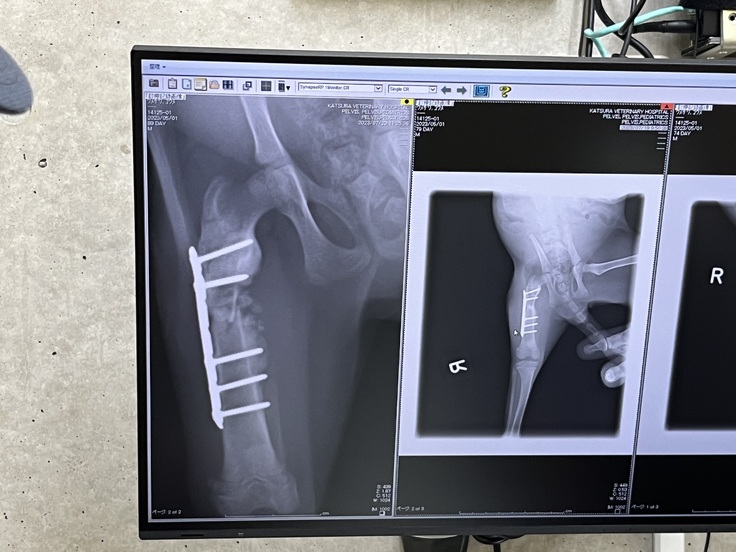

抜糸&ワクチン

今日は手術後の抜糸と、三種混合のワクチン、回虫の検便を行いました。

骨の状態は良好ですが、一応カラーはもう少しつけていて欲しいそうです。